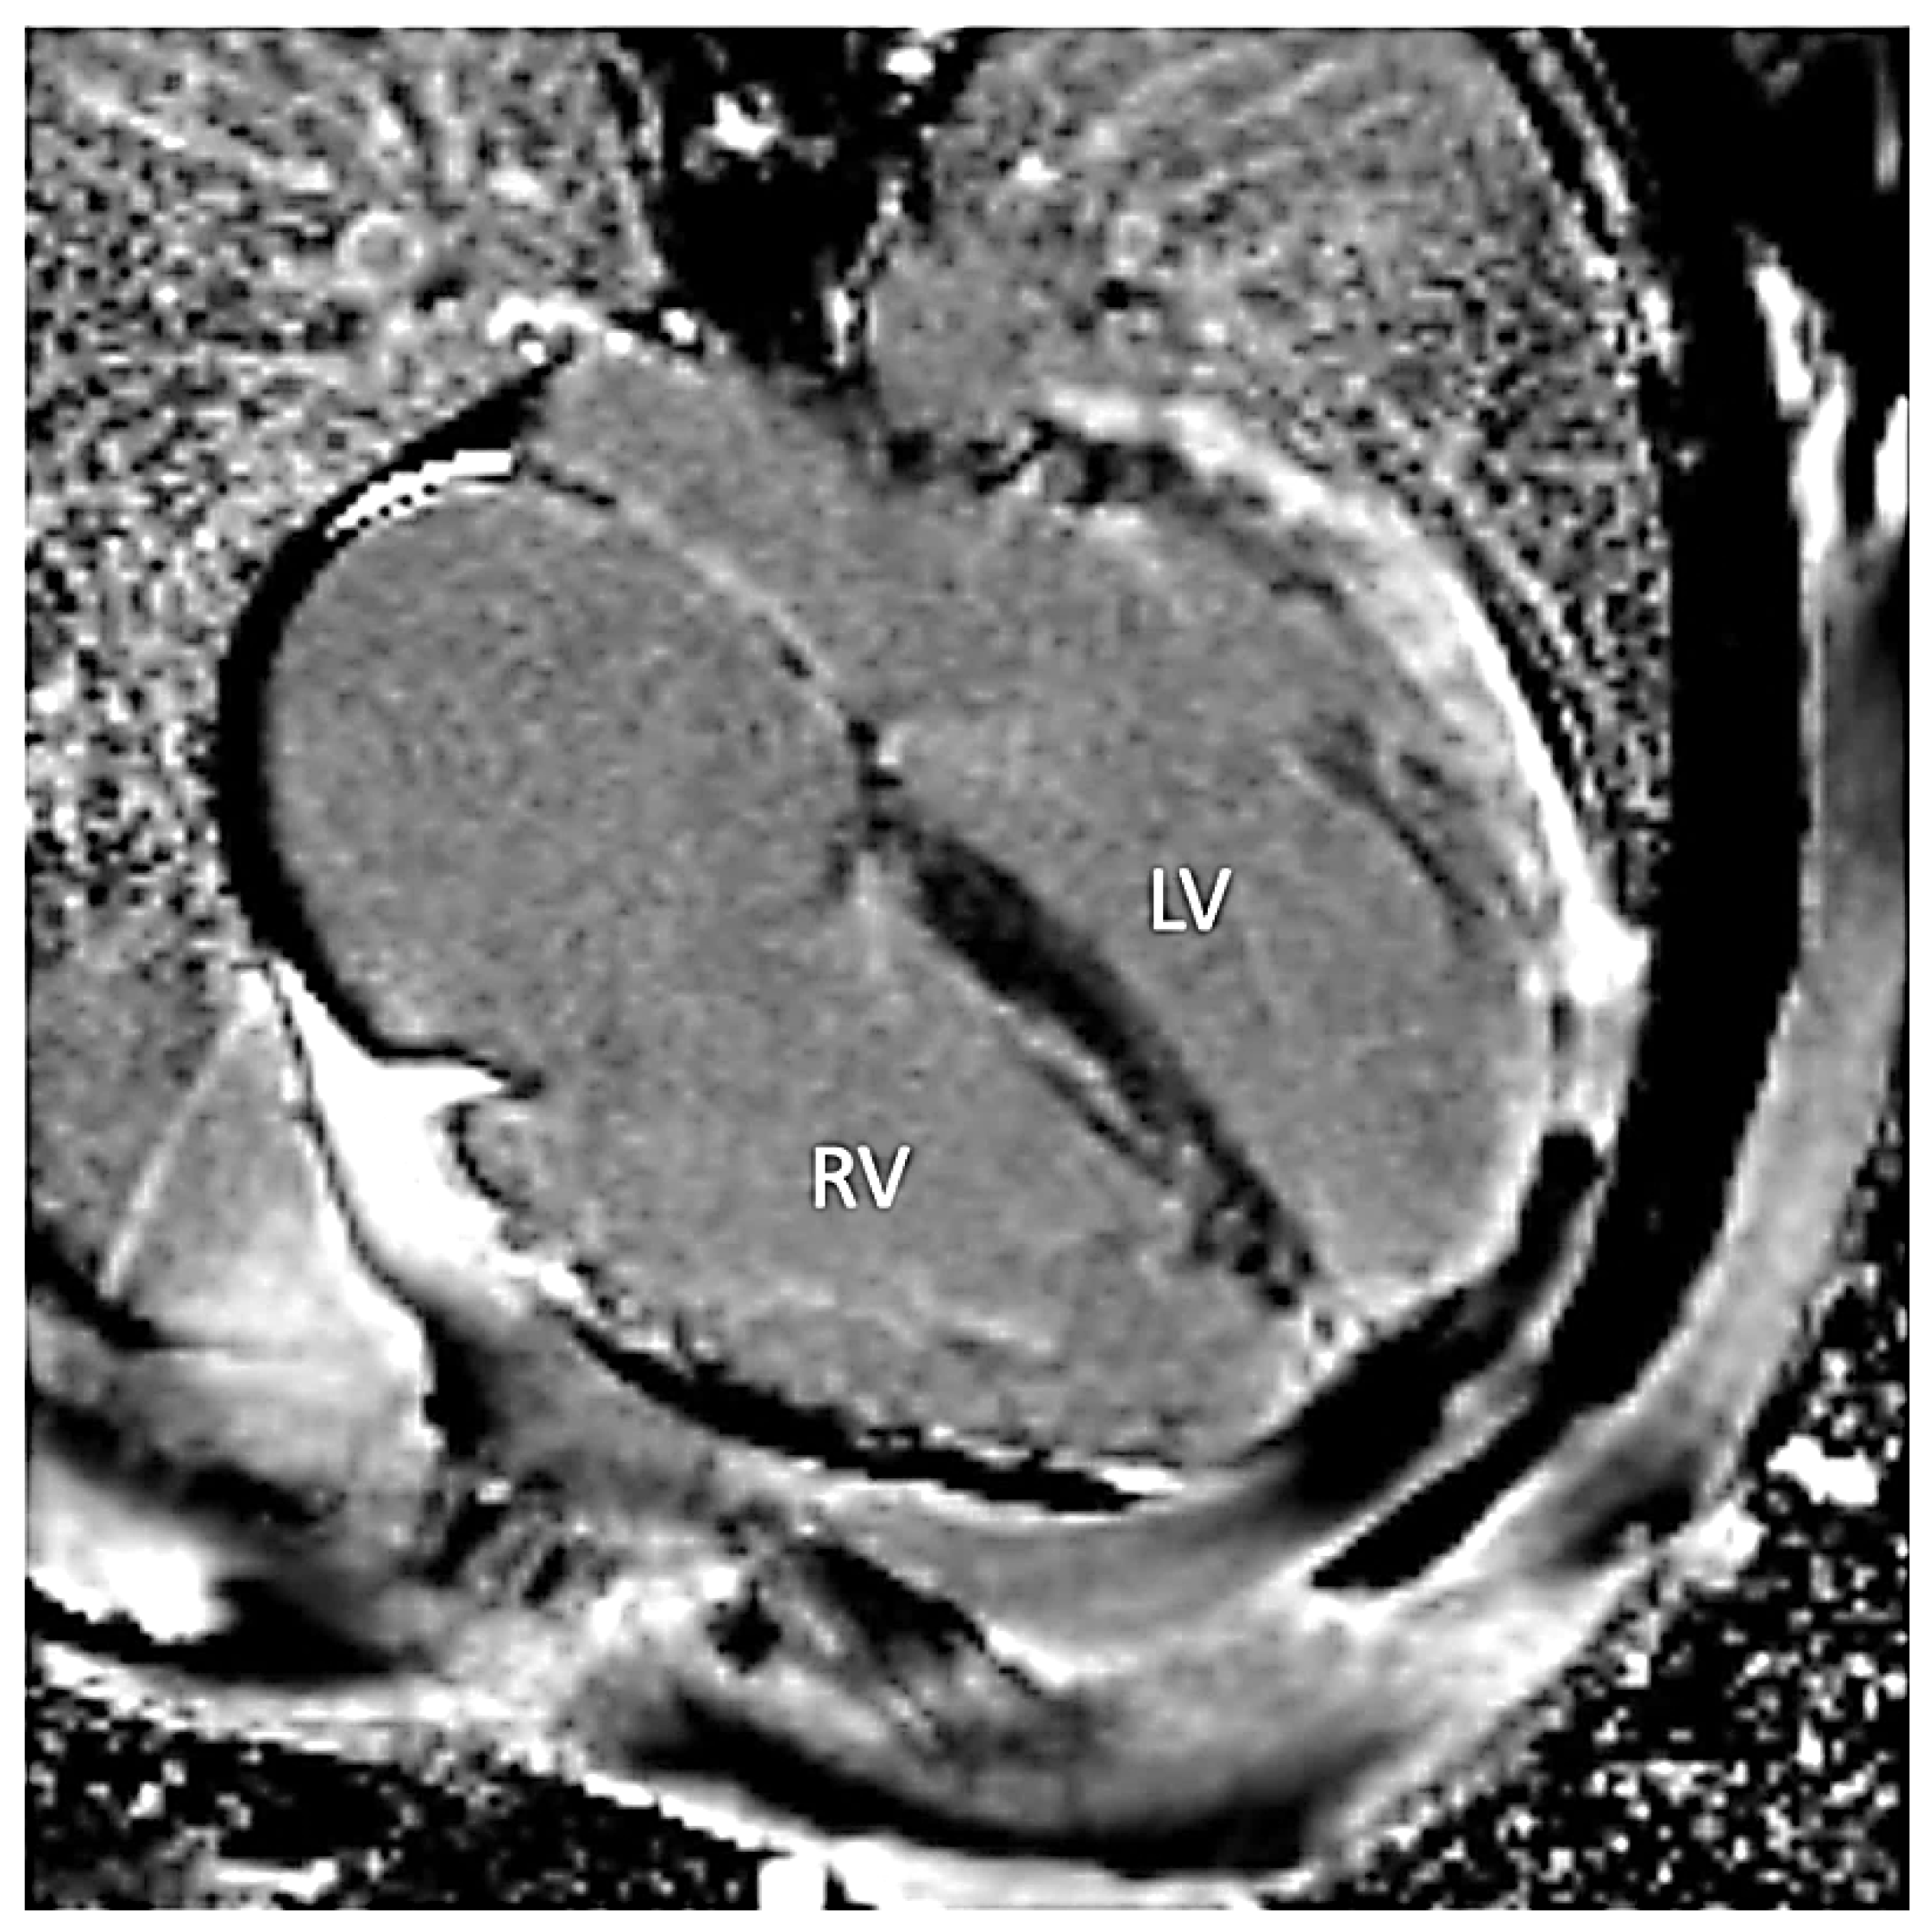

Figure 4.

Late gadolinium enhancement four-chamber image demonstrating diffuse fibrosis in the left (LV) and the right ventricles (RV).